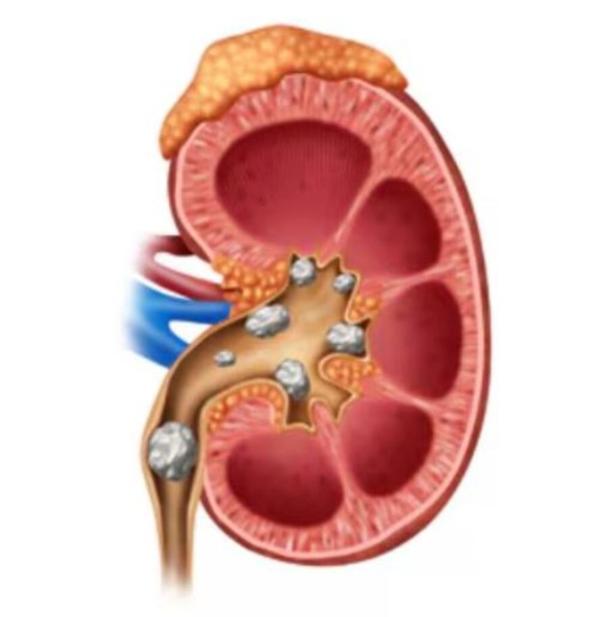

Best Kidney Stone Surgeon in Thane – Advanced Lase...

Kidney Stone Removal in Thane – Safe & Effective P...

Kidney Stone Removal Treatment in Siddharth Nagar,...

Top-Rated Kidney Stone Surgeon Near Me in Veer Sav...

Best Treatments for Kidney Stones at Our Clinic Ki...

Best Kidney Stone Treatment in Thane West – Non-Su...

Kidney Stone Pain in Thane – Advanced Treatment fo...

Exploring Advanced Urology Procedures in Thane Wes...